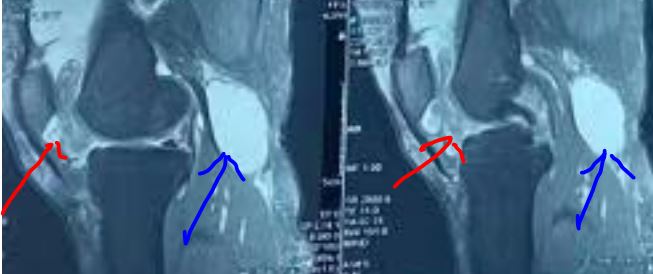

核磁共振检查(MRI )是鉴定膝关节周围肿块的金标准检查。MRI 不仅可评估囊肿与周围组织及关节内解剖结构关系,尚可显示相关关节内病变。此外,MRI 具有非创伤性,无辐射优点。

病例1 黄某,男性53岁,膝关节反复酸痛不是半年,保守治疗无效就诊,核磁检查提示膝关节腘窝囊肿,关节内退变(游离体、软骨磨损、半月板损伤),予以关节镜下关节清理+囊肿切除术。

半月板损伤